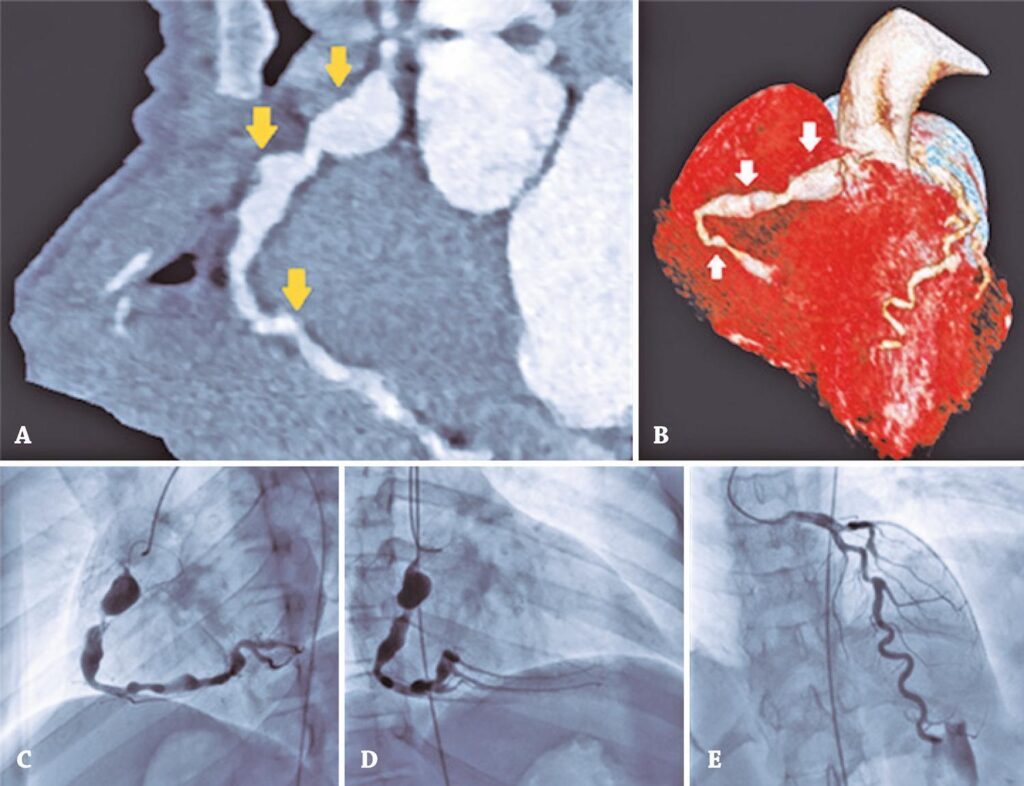

An 11-year-old male patient with a clinical history of psychomotor development delay and ventricular preexcitation required several follow-up visits at another service. No other cardiovascular-associated symptoms were described. Since the family moved home, the child was referred to our hospital. A transthoracic echocardiogram (TTE) was performed as part of standard evaluation in the first appointment, revealing anatomical changes of the coronary arteries. Further investigation included cardiac computed tomography (CT) which showed multiple aneurysmal dilations along the path of the right coronary artery (RCA), the largest measuring 10x10mm, in the proximal segment (Figure 1A). Cardiac catheterization was performed, and five aneurysms in the RCA were identified: a more proximal (18x11mm), one giant in the middle third (7x20mm) and three more distal (5.2mm; 5.5mm; 6mm in diameter) (Figure 1C and 1D). The left coronary artery presented a prominent ectasia (proximal diameter of 3mm; distal diameter of 5.4mm) of the common trunk, with a 50% stenosis of the middle third of the left anterior descending artery (Figure 1E).